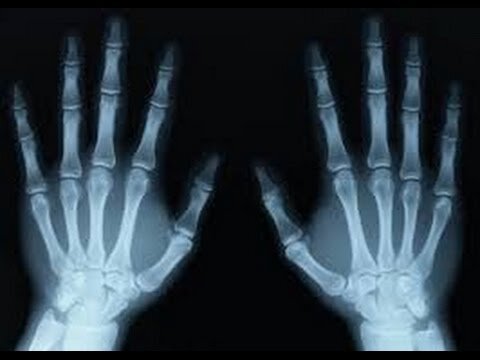

Ты видел, как делают рентгеновский снимок костей человеческого тела? Рентгеновский снимок — это изображение тени. Рентгеновские лучи проходят сквозь исследуемый участок тела и переносят на пленку тени исследуемого предмета. На обе стороны пленки наносится светочувствительная эмульсия. После съемки ее проявляют как обычную фотопленку.

Кости и другие предметы, не пропускающие лучи, выглядят на пленке темнее. В настоящее время рентгеновские лучи широко используются в медицине, науке и промышленности, оказывая большую помощь человеку.